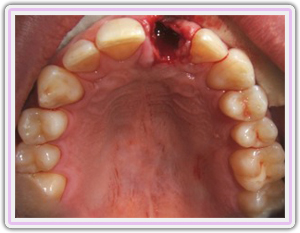

Fractured Tooth

Removal Of Tooth